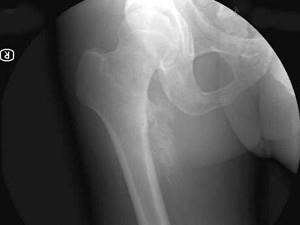

问题 35岁男性患者,因截瘫后1年,右股骨上端出现肿块2个月,渐渐地长大,行X线摄片如下图,最可能的诊断是 ( )

选项 A、截瘫后软组织骨化 B、以上都不是 C、骨肉瘤 D、软骨肉瘤 E、骨化性肌炎

答案 A